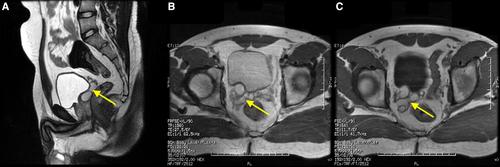

A 19-year-old male presented with 6 months of intermittent pelvic pain, dysuria, and ejaculatory discomfort. Examination was unremarkable. Ultrasonography showed right renal agenesis and a pelvic cyst. MRI confirmed a 2.8 cm cystic dilatation of the right seminal vesicle with vas deferens dilatation and absent right kidney. No ectopic renal tissue was seen. Semen analysis revealed oligospermia. Given mild symptoms and fertility concerns, he was treated conservatively with NSAIDs and antibiotics, resulting in symptom improvement within 4 weeks. Surveillance was planned.